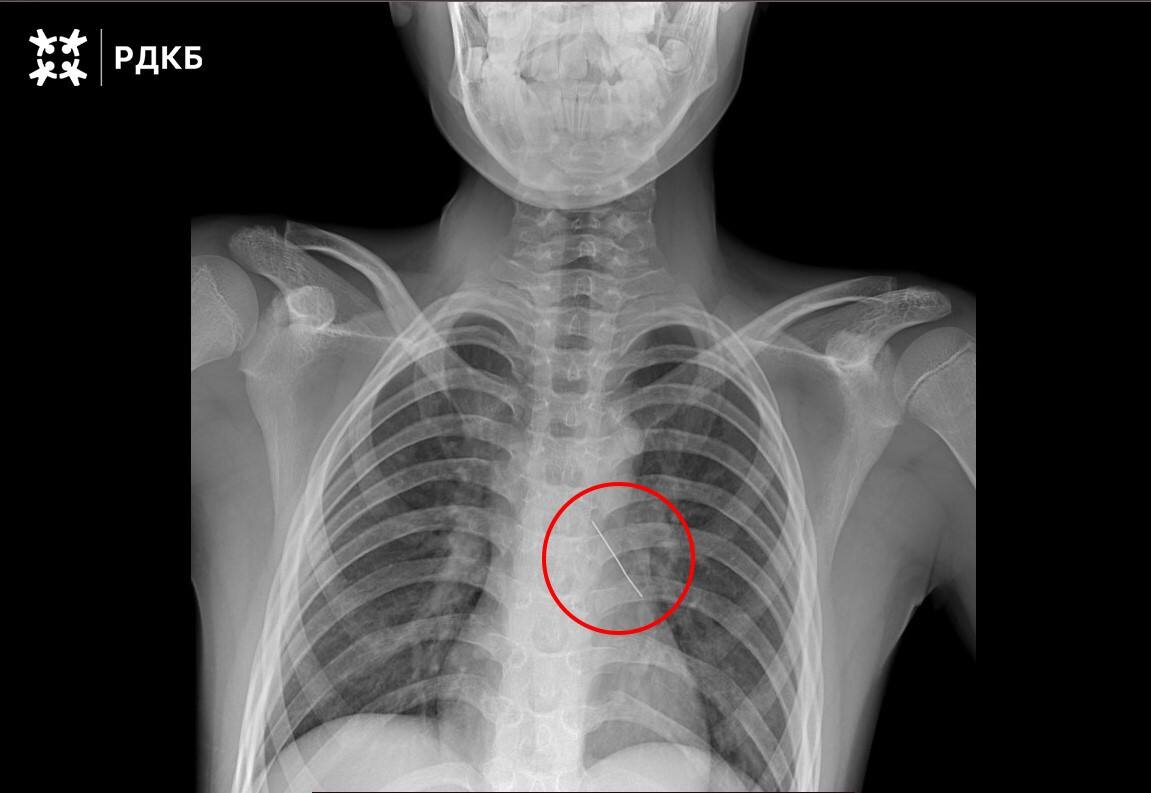

Московские хирурги спасли ребенка, вдохнувшего булавку 🚑

Московские хирурги совершили настоящее чудо, спася 11-летнего мальчика, который вдохнул булавку. Ребенка экстренно доставили бортом санавиации из Калининградской области в Российскую детскую клиническую больницу. 🚨

Операция прошла успешно: специалисты с помощью оптических щипцов аккуратно извлекли инородный предмет. Уже через три дня подростка выписали домой. 💪